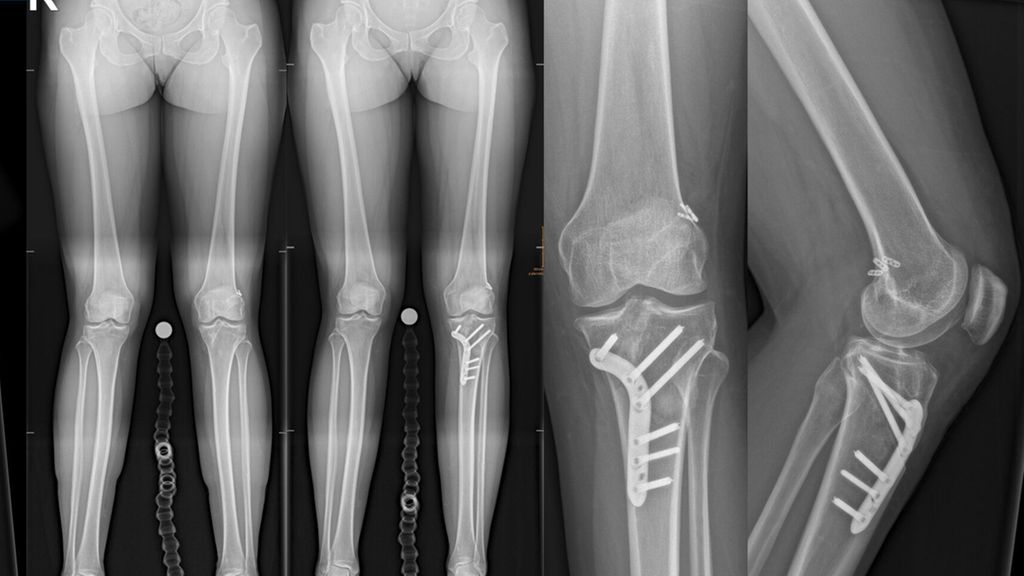

Kongenitale Deformitäten des Unterschenkels gehören zu den seltenen, aber medizinisch bedeutenden und operativ herausfordernden Diagnosen der Kinderorthopädie. Eine differenzierte ...

Die Herstellung eines symmetrischen Gangbilds sowie die Verbesserung der kinetischen und kinematischen Gangparameter im Gangzyklus stellen das Hauptaugenmerk in der Behandlung von ...